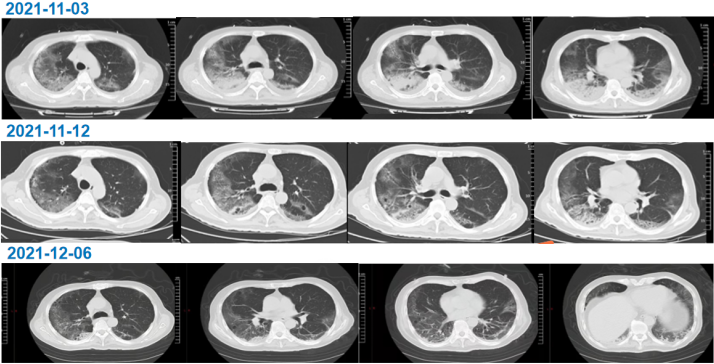

治疗3 d后,白细胞计数、C反应蛋白、降钙素原均降至正常;但患者气短症状无明显减轻,复查影像学检查无明显改善(图3)

图片

3   患者胸部CT(2021-11-03)

影像学变化

经过治疗,患者双肺磨玻璃样改变较前有所吸收,12月6日随访CT可见双肺间质性改变较前明显改善(图6)

6  患者影像学变化